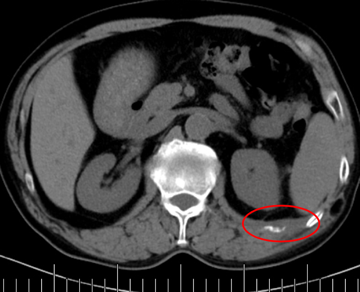

老年男性,68歲,肺癌術(shù)后肋骨轉(zhuǎn)移,痛疼難忍。

左側(cè)肋骨轉(zhuǎn)移

當日痛疼緩解